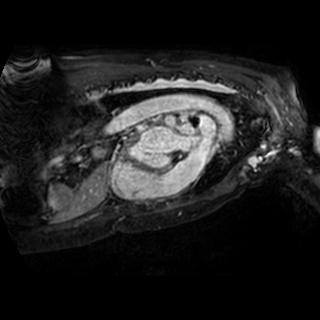

The integration of deep learning systems into healthcare has been hindered by the resource-intensive process of data annotation and the inability of these systems to generalize to different data distributions. Foundation models, which are models pre-trained on large datasets, have emerged as a solution to reduce reliance on annotated data and enhance model generalizability and robustness. DINOv2 is an open-source foundation model pre-trained with self-supervised learning on 142 million curated natural images that exhibits promising capabilities across various vision tasks. Nevertheless, a critical question remains unanswered regarding DINOv2's adaptability to radiological imaging, and whether its features are sufficiently general to benefit radiology image analysis. Therefore, this study comprehensively evaluates DINOv2 for radiology, conducting over 100 experiments across diverse modalities (X-ray, CT, and MRI). To measure the effectiveness and generalizability of DINOv2's feature representations, we analyze the model across medical image analysis tasks including disease classification and organ segmentation on both 2D and 3D images, and under different settings like kNN, few-shot learning, linear-probing, end-to-end fine-tuning, and parameter-efficient fine-tuning. Comparative analyses with established supervised, self-supervised, and weakly-supervised models reveal DINOv2's superior performance and cross-task generalizability. The findings contribute insights to potential avenues for optimizing pre-training strategies for medical imaging and enhancing the broader understanding of DINOv2's role in bridging the gap between natural and radiological image analysis. Our code is available at https://github.com/MohammedSB/DINOv2ForRadiology